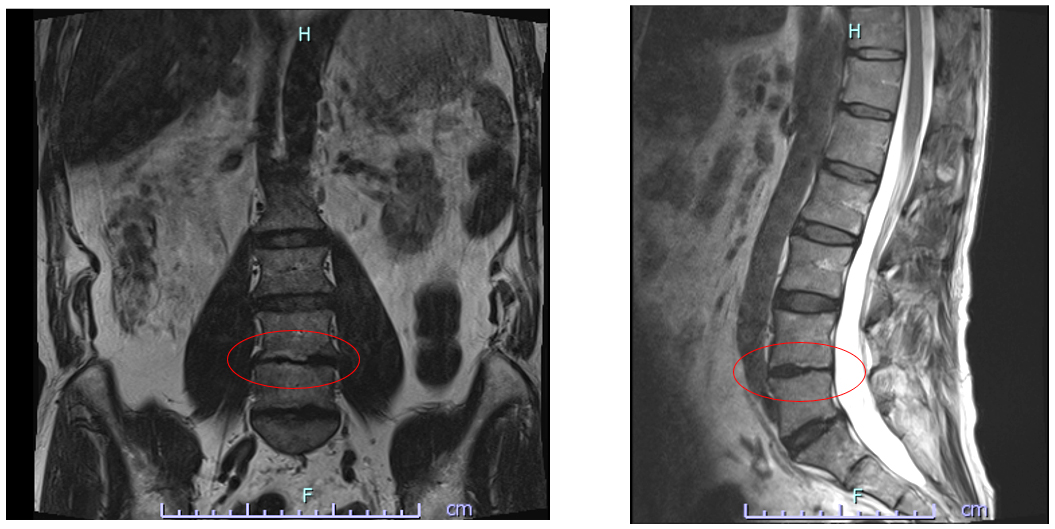

<治療前>L4/5椎間板に顕著な変性あり。

| 治療評価 | 椎間板ラジオ波焼灼術後、ペインクリニックでも治療を受けたが痛みが改善せず、不眠にも悩まれていました。 変性が顕著な L4/5椎間板腔に、Cアームを使用しX線透視下で幹細胞の直接投与を行いました。 3回の治療でほぼ疼痛が消退し、4回目以降も継続投与の予定です。 |